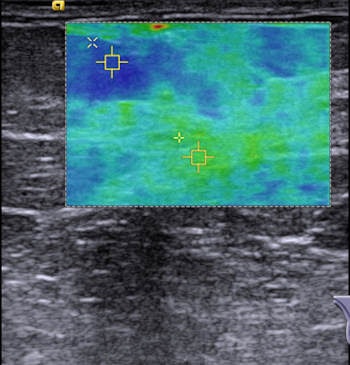

Because the speed of the shear waves propagating through the tissue is proportional to the stiffness of the tissue, a colored map in the region of interest (ROI) gives information on the tissue stiffness in the ROI, according to the authors.

B-mode ultrasound and VTIQ were performed in 132 breasts in 97 women. Mean values of VTIQ for parenchyma and fatty tissue were compared between those measured in healthy breasts and the surrounding of histologically proven benign and malignant breast lesions. The researchers also reviewed VTIQ values according to breast density measured by the American College of Radiology (ACR) categories.

In 132 breasts, the mean VTIQ values in parenchyma were significantly higher than in fatty tissue (3.23 m/sec ± 0.74 versus 2.5 m/sec ± 0.61; p < 0.0001). In healthy breasts as well as in the surrounding of benign or malignant lesions, the VTIQ values of parenchyma were similar (p = 0.12). In fatty tissue, small differences between mean VTIQ values of 2.25 m/sec ± 0.51, 2.52 m/sec ± 0.48 and 2.65 m/sec ± 0.71 (p = 0.01) in the respective groups were observed.

The researchers proposed standard values of VTIQ for healthy breast tissue: Parenchyma showed a mean of 3.23 m/sec (31.3 kPa) with a standard deviation of 0.74 m/sec (1.6 kPa) compared with 2.5 m/sec (18.8 kPa) for fatty tissue with a standard deviation of 0.61 m/sec (1.1 kPa). The difference between the two was statistically significant (p < 0.0001).